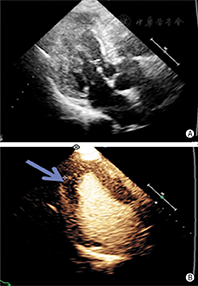

②左心室心尖肥厚:7%肥厚型心肌病为心尖明显肥厚。常规超声心动图检查因不能完整清晰显示心尖,将使15%心尖肥厚型心肌病漏诊。当怀疑是心尖肥厚型心肌病而不能被明确或排除时,应该进行心脏造影检查(图4)。心尖肥厚型心肌病左心室心腔轮廓的典型造影表现为左心室腔呈"铲子样" (spade-like)的外观,心尖部室壁明显增厚(图5);在心尖肥厚型心肌病中肥厚的心尖部造影剂灌注通常是相对减少的,与心腔内的高强度造影剂形成明显的对比[25]。

③左心室心肌致密化不全:心肌致密化不全是一种罕见的、但是越来越多地被临床认识的疾病,可导致心力衰竭、心律失常、血栓栓塞事件和死亡。室壁由增厚的运动减弱的两层心肌组成:较薄的致密化心外膜下心肌和较厚的非致密化心内膜下心肌。当怀疑左心室致密化不全,但传统的二维超声成像不能清晰显示窦隙状非致密化心肌时,造影超声心动图检查可显示突入左心室腔肌小梁之间的血池内有造影剂填充[26,27,28](图6,图7)。采用MI 0.3~0.5谐波成像,有助于更清楚显示肌小梁间隐窝。目前,孤立性左心致密化不全的诊断标准尚未统一,但通过超声造影显示非致密化心肌厚度与致密化心肌厚度比值> 2时有助于该病的确诊。